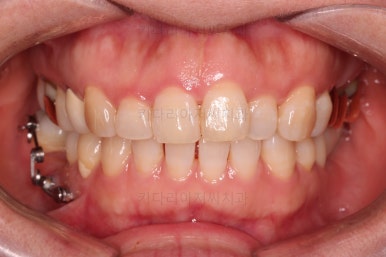

최종 사진을 보여드리겠습니다.

깔끔하게 마무리가 되었네요.

전후 비교입니다.

환자분도 치료에 만족하시어 미적으로 보기싫은 다른 금니들도 하나씩 교체하고 계신 중입니다.